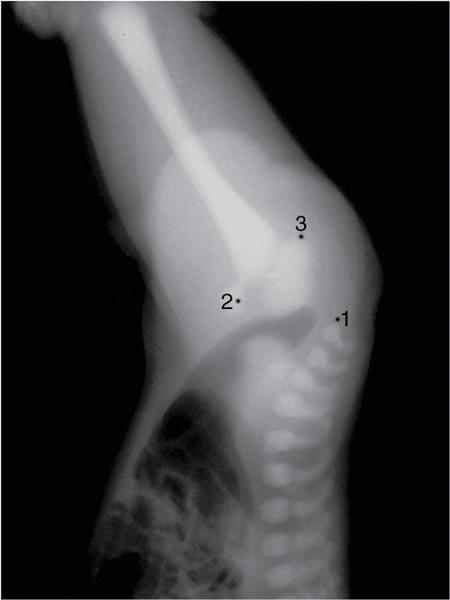

MISCELLANEOUS PAEDIATRIC RADIOGRAPHY – TECHNIQUES AND INTERPRETATION: SKELETAL SURVEY Padma V. Badhe The skeletal survey, generally performed in children, is a set of radiographs done in order to evaluate the entire skeleton. A skeletal survey, commonly used to evaluate skeletal dysplasias, acquired metabolic disorders and suspected child abuse, is still the key radiological investigation for the same. Hence, an explicit understanding of the technique along with the common disorders forms the basis of making a diagnosis in these paediatric pathologies. A skeletal survey is done for various skeletal dysplasias, non-accidental injury (battered baby syndrome) and suspected child abuse. It can also be done in cases of metabolic bone diseases, disseminated infections, multiple myeloma, eosinophilic granuloma. It is also used in evaluation of metastatic bone diseases and polyarticular arthropathy. Orthogonal views of the skull, spine, pelvis and one extremity are taken, preferable in standing position. For preterm babies/newborns, AP and lateral views of babygram may be taken. Projections: For skeletal dysplasias: Additional views: Both extremities may be taken if epiphyseal abnormalities and limb asymmetry is present. Focused views for specific pathologies may be taken. When a diagnosis remains uncertain, 1 year follow up is usually recommended. For preterm babies/newborns: AP and lateral views of babygram may be taken with additional specific views for extremities. For suspected non-accidental injury (NAI): AP and oblique view of chest is taken for better evaluation of the ribs. AP view of abdomen with pelvis. Both upper and lower limbs are evaluated. In lower limbs, two projections in AP and lateral (one with both femur including hip and knee joints; and another for foot and ankle) is taken. AP and lateral views of whole spine, skull. Oblique view of hands. A babygram should be avoided in cases of NAI, as subtle fractures are easily missed. Proper legal documentation while taking the views is very important and ideally two health care professionals must be present. For metabolic disorders: entire skeletal survey is usually not required. Specific views of hands, knees and spine may be taken with additional views depending on the suspected pathology. Centring point: Varies according to the part being examined. Angulation, collimation and orientation: Varies according to the part being examined. Images must be well collimated to obtain lower radiation dose. Detector size: Varies according to the part being examined: 8″ × 10″, 10″ × 12″, 11″ × 14″. Exposure: Ideally high kVp images are taken to reduce radiation dose. But in suspected NAI, low kVp/high mA images are recommended to better demonstrate findings. SID (Source Image Distance):100 cm Grid: Grids are not routinely used to image spine, pelvis, skull and abdomen in children. Radiation dosage: 0.3–3 mSv Essential image characteristics: Adequate spatial resolution, high signal to noise ratio, low kVp (50–70) for high contrast should be done. Excellent bone and soft tissue details are required. The presentation of skeletal dysplasia can range anywhere from minimal stunting of growth and bowing of limbs to severe dwarfism and multiple fractures. Knowledge of the commonly encountered dysplasias with an approach to arrive at a diagnosis is vital in any Radiologist’s practice The following flow chart summarizes the classification of important skeletal dysplasia: The following table summarizes the various dysplasias affecting the axial skeleton: TABLE 7.5.1.1 The following flow chart summarizes the working approach to skeletal dysplasias: Osteopetrosis (Albers-Schonberg disease/Marble bone disease) (Fig 7.5.1.1): Osteopetrosis clinically presents with anaemia/thrombocytopenia or cranial nerve compression. Radiological features include generalized increase in bone density with loss of medullary space. However, cortico-medullary appreciation with cortical thinning is also rarely seen. Bone within bone appearance with Erlenmeyer flask deformity is also noted. Pyknodysostosis (Figs. 7.5.1.2 and 7.5.1.3): patient presents with short stature. Unlike osteopetrosis, there is no anaemia. Radiographs show generalized increase in bone density with preserved medullary canal. There is mandibular hypoplasia with obtuse angle. Acro-osteolysis is also a feature. Dental caries with osteomyelitis of the jaw may be seen. Sclerosing dysplasia presenting as wavy undulating new bone formation. Usually monomelic, lower limb and along one side. The classic appearance is described as Dripping candle Wax sign. It is a Sclerosing dysplasia with radiological features of symmetric juxta-articular involvement in epimetaphyseal region. They are 1–10 mm in diameter and uniform in size. No metabolic activity is seen on bone scans. This skeletal dysplasia shows diffuse decrease in bone density with paper-thin cortex. Fractures heal in normal time but shows callus with poorly cellular matrix. Wormian bones and enlarged sinuses may be seen. Codfish vertebra (Biconcave vertebra) may be seen. Metaphyseal corner fractures are not seen in osteogenesis imperfecta that helps to differentiate it from battered baby syndrome. There are four types of OI out of which type one is most common (Figs. 7.5.1.6 and 7.5.1.7). The radiological features of MPS include Osteopenia and Universal platyspondyly. The intervertebral disc spaces are maintained. Proximal pointed metacarpals is an important radiological finding. Hurler’s syndrome show anteroinferior beaking with short and wide metacarpals. Varus deformity of humerus is characteristically seen in Hurler’s syndrome (Fig. 7.5.1.8). Mental retardation & corneal clouding is seen in Hurler’s syndrome whereas these Hunter’s disease has normal intelligence with no corneal clouding. Morquio’s syndrome shows central beaking (Fig 7.5.1.9). This skeletal dysplasia shows normal bone density with rhizomelic limb shortening and normal trunk. Narrowing of spinal canal is classically seen with decrease in the Interpedicular distance caudally. Other radiological features include trident hand (separation of middle & third fingers), Champagne glass pelvis (short, flat ilia and small sciatic notch), bullet nose vertebra and overexpansion of skull with narrow foramen magnum (Fig. 7.5.1.10). This skeletal dysplasia is characterized by normal bone density with dwarfism and normal craniofacial skeleton. The interpedicular distance is normal. There is severe platyspondyly with anterior tonguing (disappears at older age). Other radiological features include increased disc space, short stubby metacarpals, small irregular epiphysis and widened metaphysis. Anterior tonguing is a feature of Pseudoachondroplasia. This form of skeletal dysplasia involves the spine and epiphyses (Fig. 7.5.1.11). There is normal bone density with rhizomelia. Spine and Pelvis can be involved. Premature osteoarthritis can be seen. The other characteristic features include Platyspondyly and small irregular epiphysis. There are two forms Spondyloepiphyseal dysplasia Congenital and Spondyloepiphyseal dysplasia Tarda. Spondyloepiphyseal dysplasia Congenita is Autosomal dominant and shows pear-shaped vertebrae. Spondyloepiphyseal dysplasia Tarda is X Linked recessive with heaped up vertebrae. It has two forms. The first form is Conradi Hunermann syndrome which is autosomal dominant characterized by asymmetric limb shortening with metaphyseal flaring (Fig. 7.5.1.12). The Autosomal recessive form is Fatal in first few years. Rickets: Rickets refers to deficient mineralization of the growth plate in the paediatric population due to deficiency of vitamin D. In an immature skeleton, there is abnormal mineralization at the zone of provisional calcification in the metaphysis due to osteoid deposition resulting in widening of the growth plate. The features of rickets include fraying, splaying and cupping (Fig. 7.5.1.13). Fraying denotes indistinct margins of the metaphysis whereas splaying denotes widening of metaphyseal ends. Term ‘Cupping’ is used for increased concavity of the metaphysis. These findings are typically seen involving areas of active growth (e.g. distal femur and proximal tibia in the knee) Bowing is a result of associated osteomalacia leading to weakening of weight-bearing lower limb bones. Other bone deformities such as genu valga, genu varum, protrusio acetabuli can also be seen. The lower ribs may also be drawn inwards inferiorly by the attachment of the diaphragm this is called Harrison’s sulcus. Scurvy: Scurvy is a result of dietary deficiency of Vitamin C (ascorbic acid). The classic presentation is that of a patient with an increased bleeding tendency and osteopenia with poor wound healing. Features of scurvy include generalized osteopenia with cortical thinning termed as ‘pencil-point’ cortex. Other radiological findings include the periosteal reaction due to subperiosteal haemorrhage. Expansion of the costochondral junctions occurs forming scorbutic rosary. Bleeding into the joint spaces may result in hemarthrosis. Circular, opaque radiologic shadow surrounding epiphyseal centres of ossification may result from bleeding (Wimberger ring sign) (Fig. 7.5.1.14). Frankel line may be seen. It represents dense zone of provisional calcification. Lucent metaphyseal band is seen underlying Frankel line called as Trümmerfeld zone. Metaphyseal spurs may be seen that result in cupping of the metaphysis (Pelkin spur). Pelkin fracture (metaphyseal corner fracture) can also be seen. Images obtained must be of good resolution with adequate bone and soft tissue details. Additional views: They have already been described in positioning. CT Brain in can be done in cases of NAI to look for subdural hematomas. A skeletal survey is the first-line imaging modality for evaluation of skeletal dysplasia, nonaccidental injury and metabolic bone diseases. The skeletal survey must be tailored according to the respective indication. It helps to characterize syndromic patterns in skeletal dysplasias, with evaluation of complications. In cases of diagnostic dilemmas, additional focused view and occasionally yearly follow-up is recommended. A high index of suspicion is needed in utilizing skeletal survey as a diagnostic modality in NAI. At the same time, one must also remember the legal and social implications of making this diagnosis. BABYGRAM Babygram is a colloquial term used for a radiograph of the whole body of a newborn or just the chest and abdomen (thoracoabdominal babygram) on a single image. As the name suggests it is a rather non-targeted study. It is most commonly requested after line placement. Evaluation of skeletal abnormalities in a deceased foetus is typically performed using anteroposterior and lateral views of a babygram. It helps in pointing out skeletal causes of death in stillborn or dead foetuses. This will help the treating physician and parents understand the reason for baby’s death. This will also help in future genetic counselling of the couple. Sometimes chest or abdominal radiographs of the baby are requested but due to radiographers error or inexperience with small babies, there is inclusion of the region not to be assessed leading to a false babygram. Babygram is most frequently done after line placement in neonates, to view the position of the umbilical vein or artery catheter and to confirm appropriate placement. It is a useful modality in skeletal dysplasias (Fig. 7.5.1.15) like osteogenesis imperfecta, thanatophoric dysplasia and chondrodysplasia punctata. It can also be used for skeletal deformations probably caused by foetus akinesia and in cases of Caudal regression syndrome. In stillborn foetuses, it is used for evaluation of skeletal dysplasias prior to an autopsy (Fig. 7.5.1.16). It is also used in screening for surfactant deficiency and in cases of Necrotizing Enterocolitis in preterm babies where it can help to see the bowel dilatation, intramural and portal venous gas. It can be done in aneuploidies like trisomy 18 and in cases of sudden infantile death syndrome. All the essential equipment and room need to be prepared including the exposure factor. This should be done prior to placing the baby on the table to prevent any neonatal heat loss. Ensure that the baby is correctly identified. Give brief explanation to the patient’s parents regarding the procedure, its risks and benefits. Ensure that the accompanying relative is not pregnant (if female). Parents/guardians/nurses should be instructed to hold the baby with arms above the head and legs straight down. Sandbags/tapes can be used to immobilize the baby. Avoid taking the radiograph when baby is crying. Normal appearance: The endotracheal tube should lie in the lower third of trachea, distance can vary with position of baby’s head. Umbilical artery catheter has an inferior dip along the internal iliac artery, which then turns superiorly along the aorta. The tip should lie in the mid-thoracic aorta (T6–T10) or lower (L3–L4) away from aortic branches to prevent any thrombosis. Umbilical venous catheter does not have the inferior curvature, but rather a posterolateral angulation to the right near the liver through the ductus venosus. The tip should lie in the superior IVC or right atrium at T8/T9 vertebral level (Fig. 7.5.1.17). Portal venous gas may be seen initially after insertion. In a stillborn foetus, the approximate gestation age of the foetus and corresponding ossification centres must be known. In early gestation, the lack of appearance of an ossification centre may be mistaken for skeletal dysplasia. Both chest and abdomen should be included. In a rotated patient, the distance between the spinous process to medial end of clavicles will be asymmetric. The medial end of clavicle should overlap the lung apex, if above, suggests lordotic image. Motion artefacts to be reduced as much as possible. A crying neonate may result in an expiratory film, and hence must be evaluated accordingly. In evaluation of skeletal dysplasias in the newborn, additional views of skull and hand have to be obtained. Baby gram is a useful diagnostic investigation for position of the paediatric umbilical catheters. It helps in general survey in skeletal dysplasia (Fig. 7.5.1.18). It is a simple, effective study in deceased foetus for diagnosis and further counselling, sometimes obviating the need for an autopsy. As baby gram is a non-targeted study, it increases the dose of radiation for the baby. As the exposure settings remain same for the entire body of the baby, the quality of the image decreases. This increases the chances of missing subtle findings. The babygram in a neonate is currently used to localize umbilical catheters. In stillborn fetuses, it is still an important study for documenting and confirming skeletal dysplasias. Understanding the normal appearance as per gestation age and patterns of various common skeletal dysplasias is essential for evaluation. Being a non-targeted study, it should not be used as an alternative study to evaluate the chest or abdomen considering radiation exposure and poorer image quality. INVERTOGRAM Invertogram was first described by Wangensteen and Rice in 1930. It was used as a first investigation to be ordered in evaluation of infants with clinically diagnosed or suspected Anorectal Malformation (ARM). ARM is a serious but surgically treatable congenital malformation with approximate incidence of 1 in 5000 live births. Though the diagnosis of this condition is based on clinical history and physical examination, imaging plays an important role in deciding the type of ARM, and associated complications to aid in management. International classification of anorectal malformations is as follows. Syndromic association is seen as a part of VACTERL defects, trisomy 21 13 and 18, Klippel Feil syndrome, cat eye syndrome etc. The main indication of Invertogram is to evaluate anorectal malformation in a neonate. A radio-opaque marker is placed over the external anal opening. Infant is held inverted by holding both thighs, maintaining this posture for at least 5 minutes before taking an X-ray in true lateral position (Fig. 7.5.1.19). Exposure is made during inspiration. The Invertogram should ideally be done 24 hours after birth as, the rectal gas may not reach the terminal segment if study is done too early. Pubo-coccygeal line (PCL) is drawn from upper border of pubic symphysis (which corresponds to centre of pubic bone on lateral X-ray) to sacrococcygeal junction. I point is the inferior most point of ischial ossification centre. A line which is drawn parallel to PC line passing through the I point is called I line. ‘A’ point is represented by marker placed at anal pit. The position of rectal pouch gas shadow is observed with respect to these lines and appropriate diagnosis is made (Fig. 7.5.1.21). A diagnosis of high ARM is made when gas shadow of rectal pouch is cranial to PCL. If rectal pouch gas shadow is in between PCL and I line, it is called as intermediate ARM and if it is caudal to I line, it is diagnosed as low ARM. Gas in urinary bladder or vagina or beaking of gas shadow of rectal pouch indicates fistula into one of these sites. Associated congenital abnormalities like spinal defects are also looked for in the invertogram (Fig. 7.5.1.22). Invertogram done too early (less than 24 hours) may not demonstrate rectal gas. Meconium plugging the terminal segment gives false position of the rectal gas. Positioning can cause discomfort to child and an irritated crying child actively contracts the sphincter muscles, pushing the gas shadow higher. Rectum may be pulled cephalad due to gravity in inverted position. The rectal gas may escape through an associated fistula. Erroneous interpretation can also occur due to sacral anomalies and when gas in vaginal cavity is misinterpreted as distal rectal gas. Both ischial bones should superimpose and terminal blind loop should be well distended. It is an easily available modality and can be done quickly, does not require additional equipment. It has lesser radiation dose as compared to CT invertogram. It provides a rough guide as to the type of ARM and decides management. Higher localization of obstruction due to various causes like meconium plugging, imaging done too early etc. as described above in pitfalls. It is more uncomfortable to the baby as compared to the prone cross-table lateral view, and a crying baby contracts the puborectalis leading to erroneous results. K. L. Narasimharao et al. modified the technique and proposed cross-table lateral view for evaluation of infants with ARM’s which has shown equal or better information and has now replaced invertogram (Fig. 7.5.1.23). Prone cross-table lateral view is considered equivalent or even better in determining the level of anomaly. Positioning is in this view is prone in genupectoral position (at least for 3 minutes). It is taken in true lateral and during inspiration. The lines used to delineate types of ARM is essentially the same as in an invertogram. It is preferred over invertogram as relatively easy positioning of the infant and less discomfort allows for better cooperation of neonate during the study. It also eliminates the effect of gravity. ARM with fistula is better delineated as, in an invertogram, fistula/gas is at the highest level and gas may escape through it. CT invertogram is another modality that delineates anatomy better but is rarely used. In the era of cross-section imaging, MRI and USG have opened new modalities for accurate diagnosis of ARM, but invertogram being readily available, inexpensive, quick and cost-effective is used as first investigation for evaluating a patient with suspected or confirmed case of ARM. Cross-table lateral view has replaced invertograms as it is more patient-friendly and equally effective. UPPER GASTROINTESTINAL SERIES Rushit S. Shah An upper gastrointestinal (GI) study is a radiographic examination of the GI tract from the pharynx to the ligament of Treitz after oral administration of contrast agent. The use of upper GI studies is gradually declining with the increasing availability of paediatric endoscopy and the challenge for the modern radiologist to work in conjunction with the surgeon and gastroenterologist to select the right patients for an upper GI series. However, the upper GI series remains the key for demonstrating many anatomical abnormalities. The upper GI series is also useful in evaluating gastro-oesophageal reflux in conjunction with 24 pH monitoring. The upper GI examination is useful in evaluating many conditions including but not limited to: